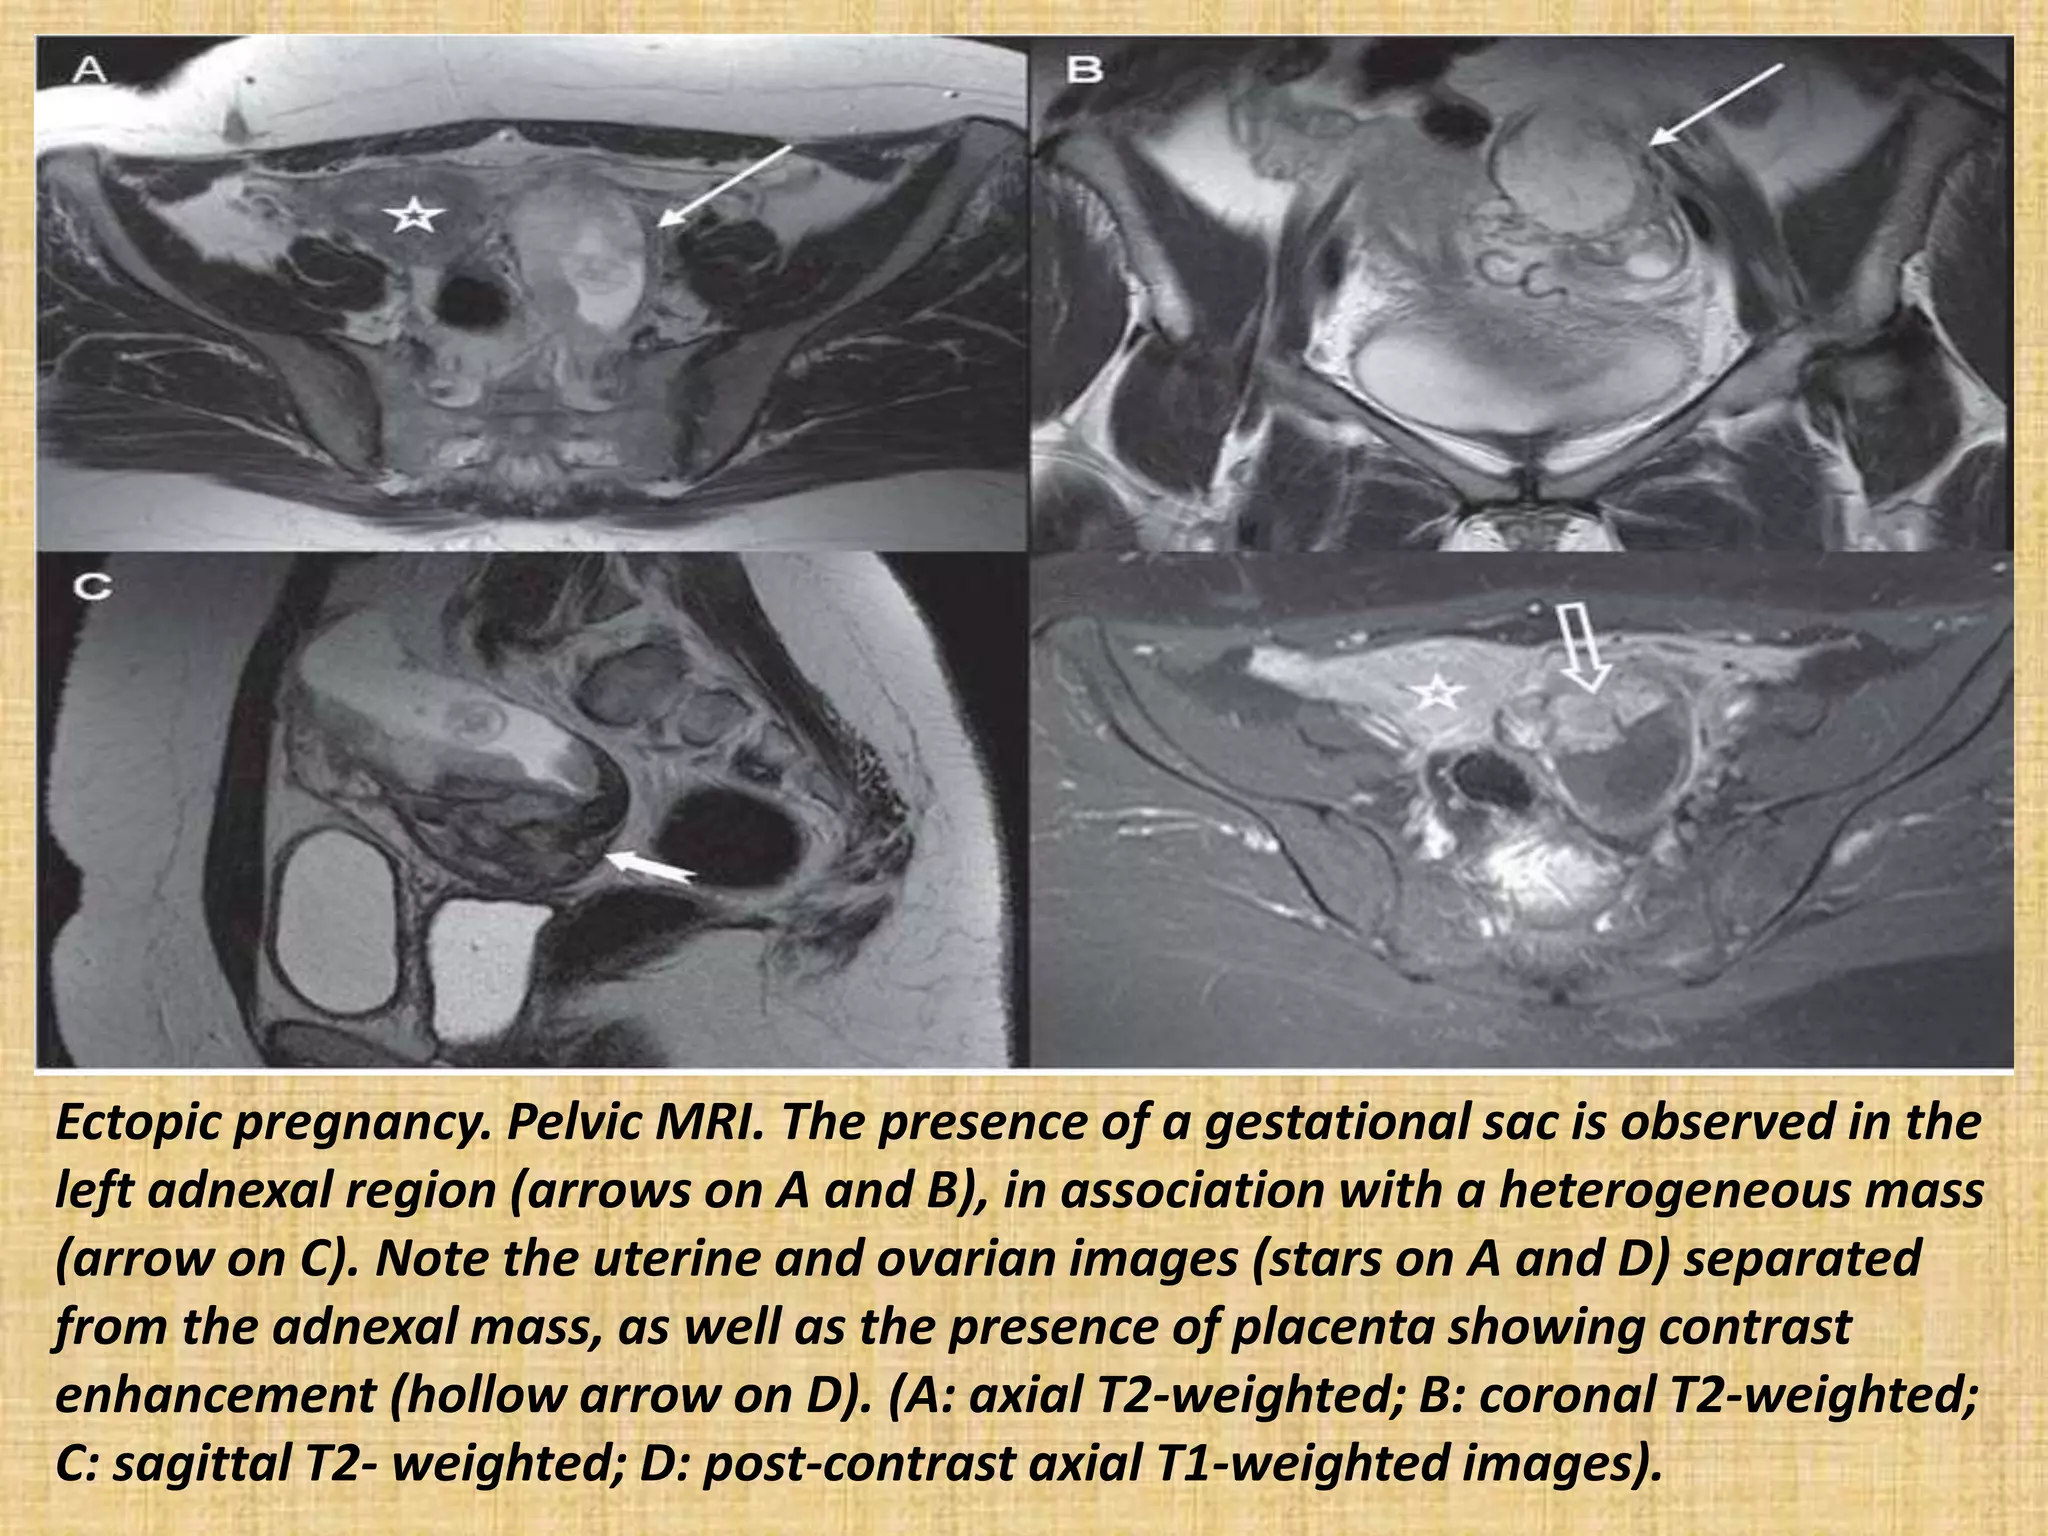

Ectopic pregnancy. Pelvic MRI. The presence of a gestational sac is observed in the

left adnexal region (arrows on A and B), in association with a heterogeneous mass

(arrow on C). Note the uterine and ovarian images (stars on A and D) separated

from the adnexal mass, as well as the presence of placenta showing contrast

enhancement (hollow arrow on D). (A: axial T2-weighted; B: coronal T2-weighted;

C: sagittal T2- weighted; D: post-contrast axial T1-weighted images).

Ectopic pregnancy. PelvicMRI. The presence of a gestational sac is observed in the left adnexal region (arrows on A and B), in association with a heterogeneous mass (arrow on C). Note the uterine and ovarian images (stars on A and D) separated from the adnexal mass, as well as the presence of placenta showing contrast enhancement (hollow arrow on D). (A: axial T2-weighted; B: coronal T2-weighted; C: sagittal T2- weighted; D: post-contrast axial T1-weighted images).